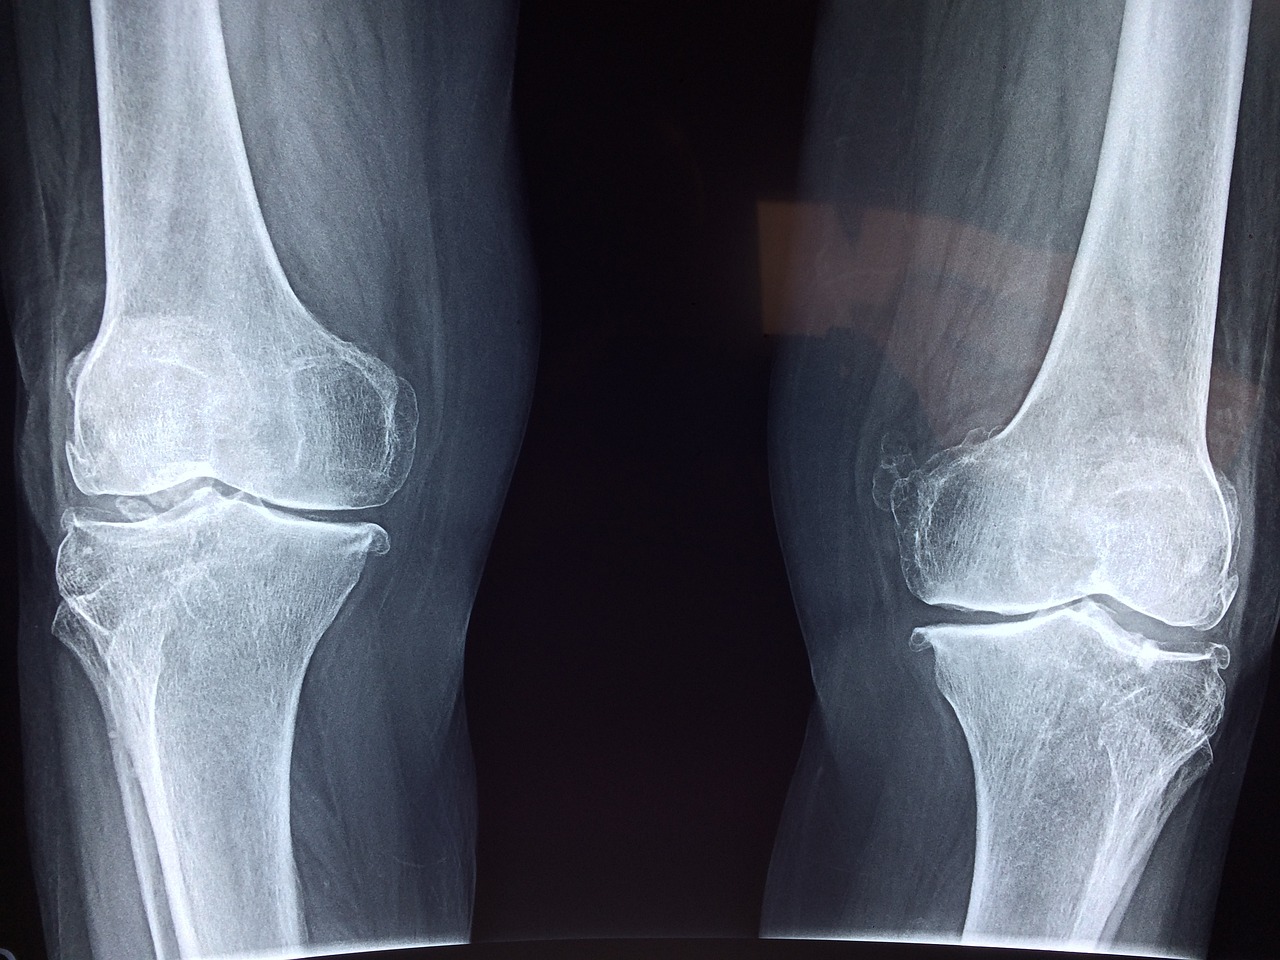

골다공증은 뼈의 밀도가 감소하고 뼈조직이 무너져 약해지는 상태로, 이로 인해 골절의 위험이 증가합니다. 골다공증은 주로 여성에서 발생하며, 노화로 인해 뼈 손실이 더 빨리 일어날 수 있습니다. 골다공증의 증상과 골다공증에 좋은 음식에 대해서 알아보겠습니다.

- 뼈의 쉬운 골절: 골다공증은 일상적인 활동이나 가벼운 부상에도 뼈가 쉽게 골절될 수 있는 상태를 만들 수 있습니다.